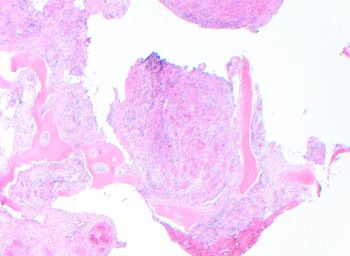

A 60-year-old male presented with a slowly enlarging, contrast-enhancing left lateral...

Case History